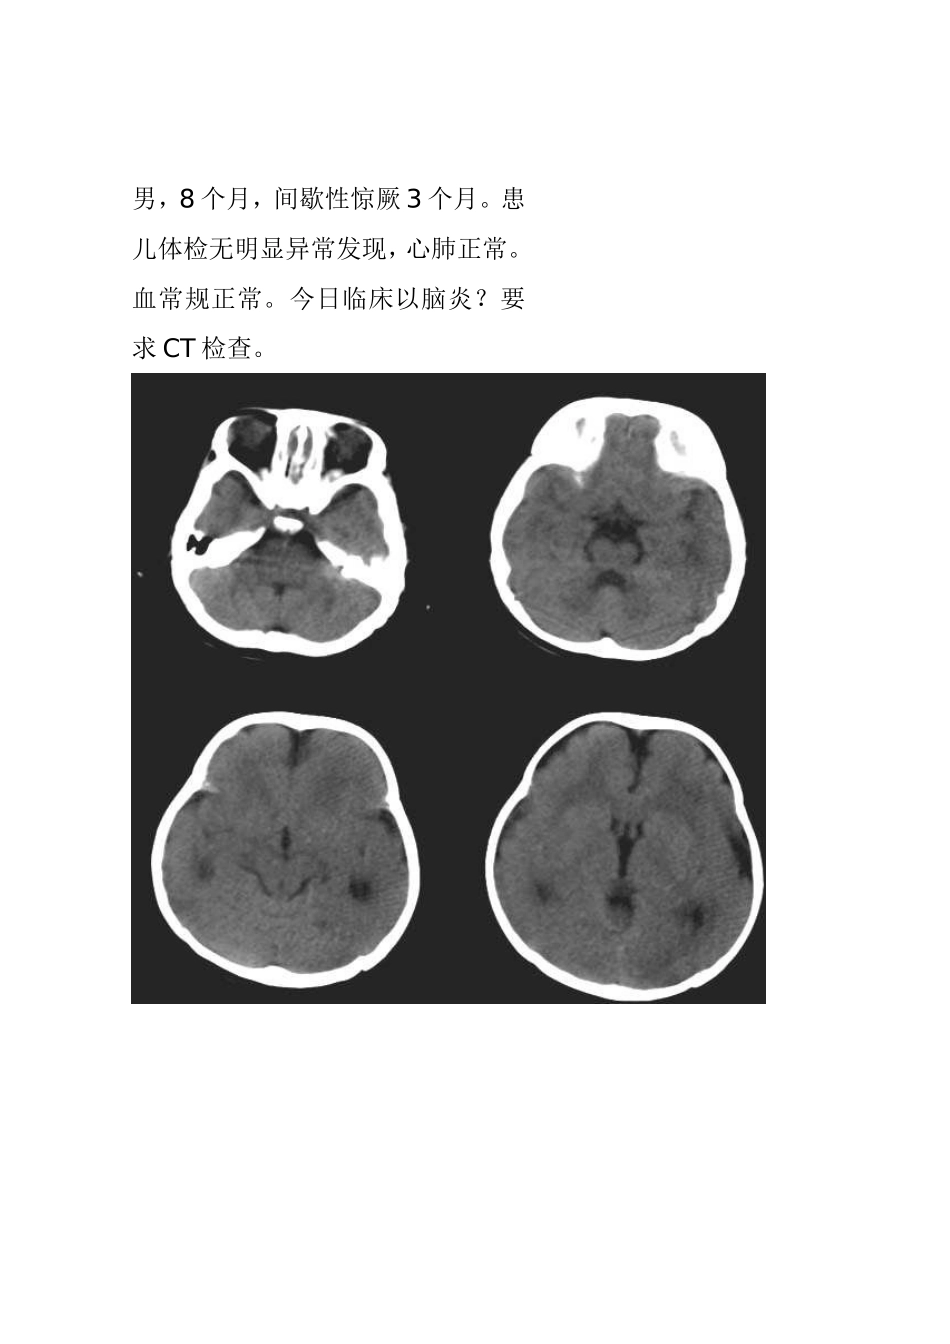

F/0.5Y。患儿主要表现为癫痫,近一个月来频发。五官尚可,头颅大小与同龄儿相比稍小,智力低下(平时家人斗小孩时目光及动做迟缓)。结果:无脑回畸形伴胼胝体发育不良男,8个月,间歇性惊厥3个月。患儿体检无明显异常发现,心肺正常。血常规正常。今日临床以脑炎?要求CT检查。平扫显示大脑半球皮质明显增厚,脑白质减少,两侧额顶脑沟少而浅,呈现巨大脑回表现,部分大脑皮质缺乏沟回,影像:巨脑回畸形。女性,22岁,左侧上下肢瘫痪21年结果:巨脑回畸形[病理]无脑回畸形和/或巨脑回畸形:无脑回畸形指大脑表面光滑,无脑回结构;巨脑回畸形指大脑停留在先天性巨脑回原始阶段,脑回宽、扁。两者仅为畸形成度不同,可同时存在于脑的不同部位。前者多在顶枕部,后者多位于额部。镜下管前者大脑皮质结构异常,皮质分层不完全或不分层,常见不成熟的神经细胞。后者皮层保留了原始皮层的4曾神经细胞结构,神经细胞分化不成熟。白质中常发现异位的神经细胞,有时呈结节状。[临床表现]无脑回畸形患儿在新生儿期常有小头畸形和轻微面部异常,以后表现出智力落后。完全性无脑回畸形者大多在2岁前死亡。巨脑回存活者常有智力低下和癫痫。[CT表现]无脑回畸形和/或巨脑回畸形,前者主要表现为脑表面光滑,脑回、脑沟消失,皮层增厚,白质减少。后者主要表现为侧裂变浅、增宽,脑回增宽,皮质增后,内表面光滑,白质减少,患侧脑室系统扩大。此外,无脑回畸形两侧裂变浅,呈“8”字形表现。[本例CT平扫]显示双侧大脑半球皮层明显增厚、表面光滑、无脑回及脑沟,皮层下白质稀少。双侧外侧裂变浅、凹陷,整个双侧大脑半球呈“8”字形表现,脑室系统扩大。前纵裂增宽、增深,与第三脑室向连通。双侧侧脑室扩大、分离。